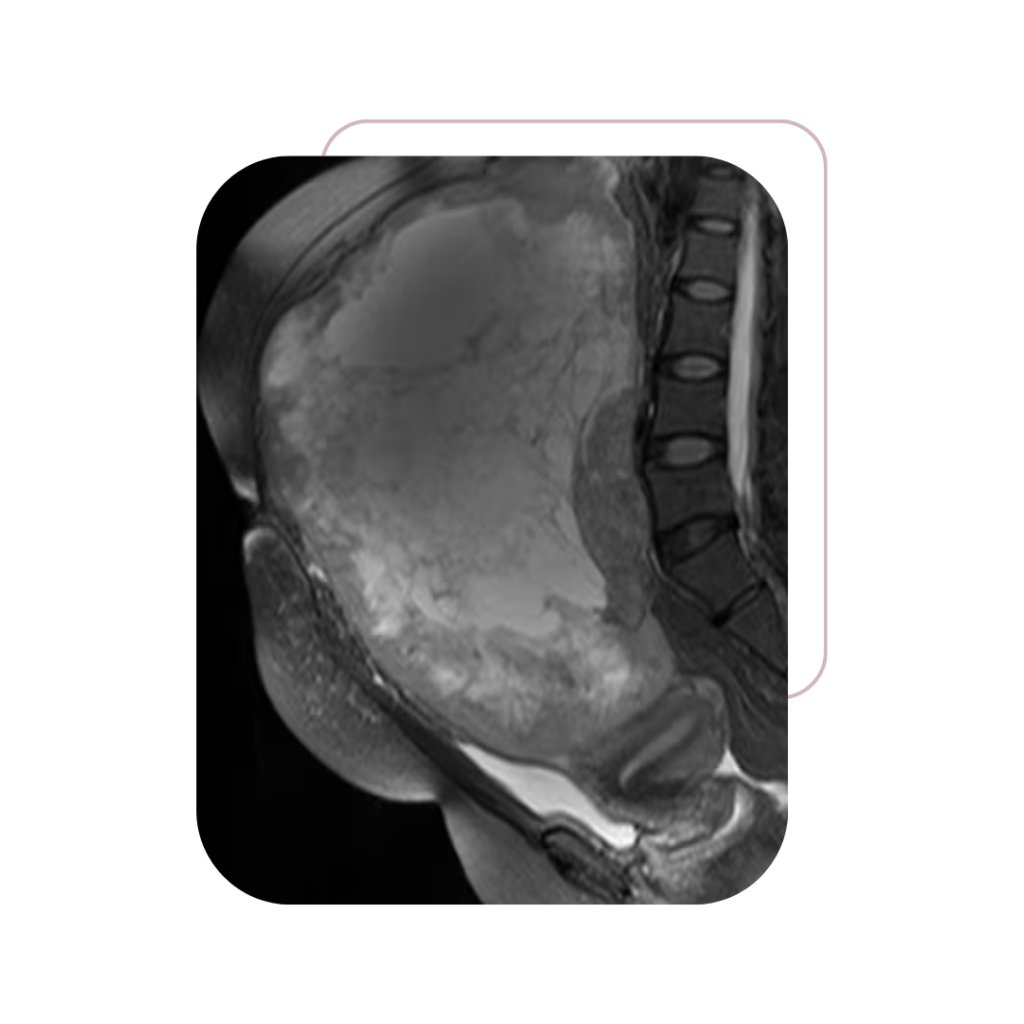

A Dra. Jacqueline Menezes dedica sua carreira ao tratamento e à preservação da saúde da mulher, com foco em cirurgias oncológicas ginecológicas seguras e minimamente invasivas.

Ginecológicos

Massas Pélvicas

e Abdominais